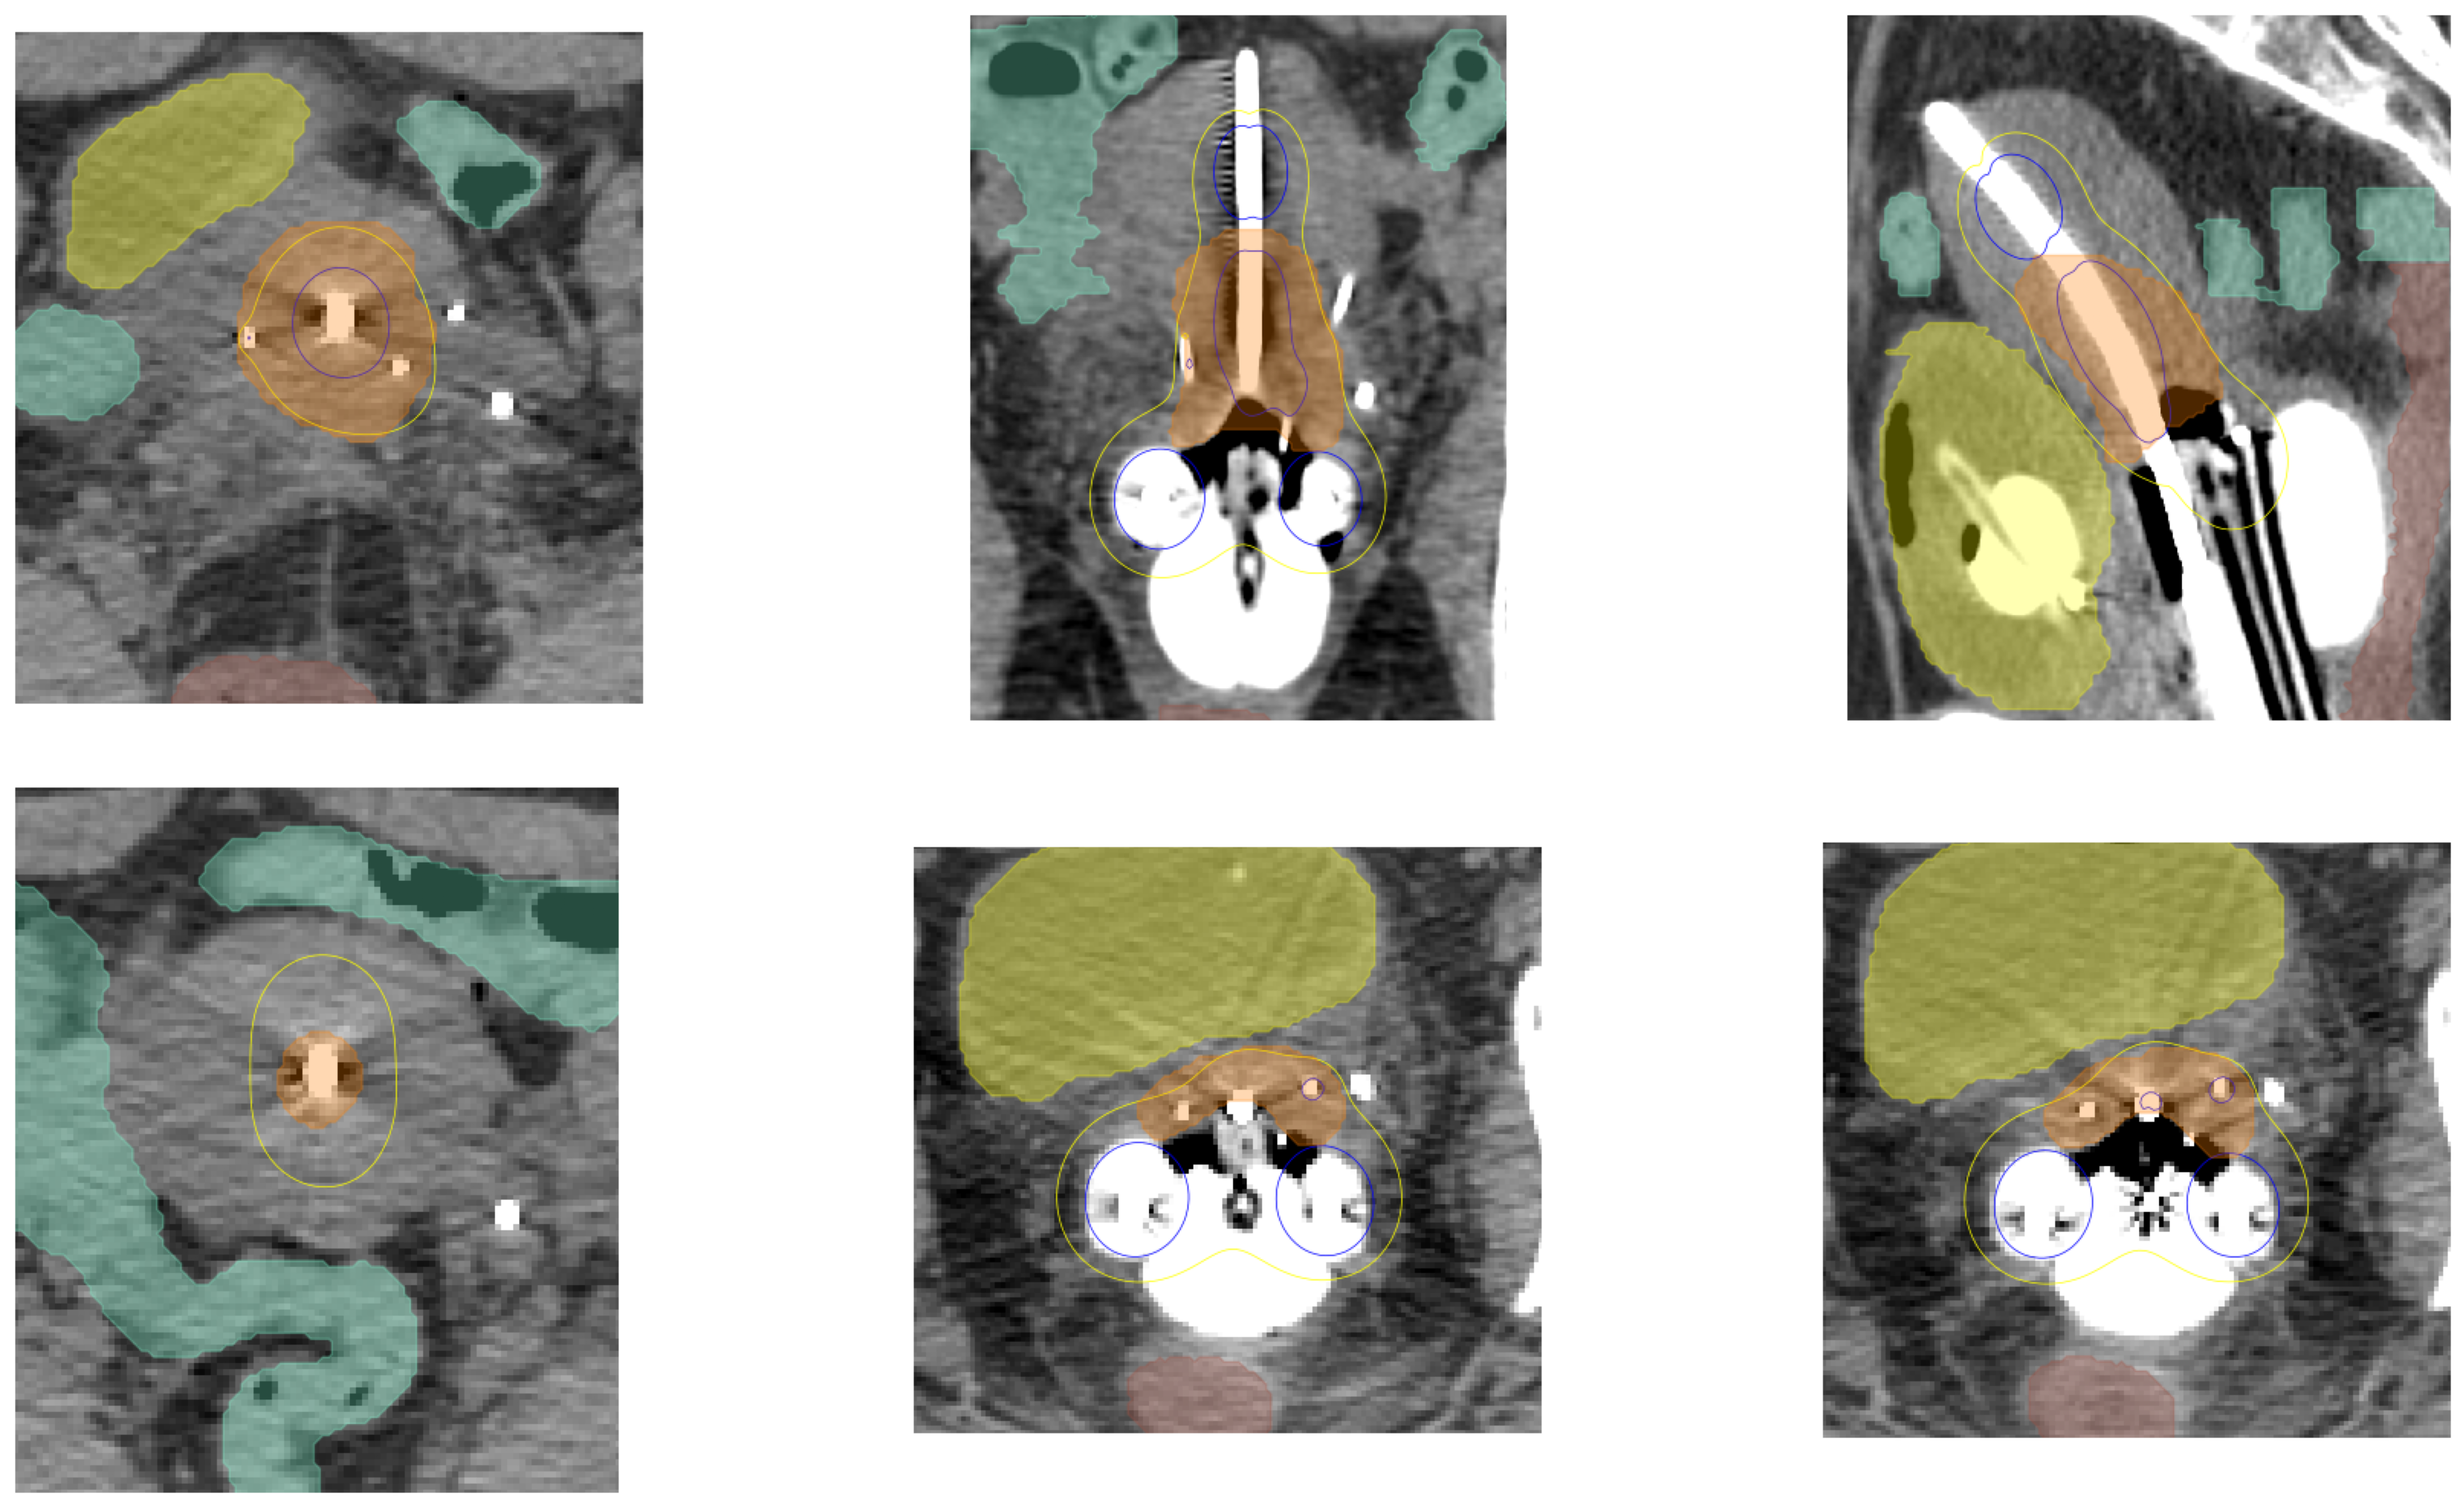

Local Tradeoffs Understanding. To facilitate independent operation from conventional treatment planning systems, we developed ALMo-Viz-Explain, an integrated visualization grid that systematically presents critical local dosimetric information. This component streamlines the evaluation workflow by minimizing the need for platform switching during plan assessment. The visualization grid employs a two-tiered structure for comprehensive plan evaluation. The upper tier presents CT slices from anatomically significant viewpoints: axial, sagittal, and coronal planes. Following established clinical protocols for HDR brachytherapy visualization333Based on standardized treatment planning protocols at the Stanford University Medical Center and aligned with American Brachytherapy Society guidelines., we identify key anatomical landmarks: the central tandem applicator plane, the characteristic pear-shaped isodose distribution plane, and the optimal tandem applicator visibility plane – displayed from the axial, sagittal, and coronal viewpoints, respectively. The lower tier focuses on regions of potential toxicity concern, displaying axial slices corresponding to peak dosage regions in cervical, vaginal mucosa, and needle regions (HSRs). Figure 4 demonstrates the ALMo-Viz-Explain interface, which allows the clinician to take a deeper look into a single treatment plan and quickly glean the critical information.

Refer to caption

Figure 4: Local Tradeoffs Visualization. Interpretability figures, ALMo-Viz-Explain, for a single treatment plan are shown. The top row displays the most salient views from the axial, sagittal, and coronal perspectives, and the bottom row displays the axial frames with the hottest regions in the cervix, vaginal mucosa, and needle regions.